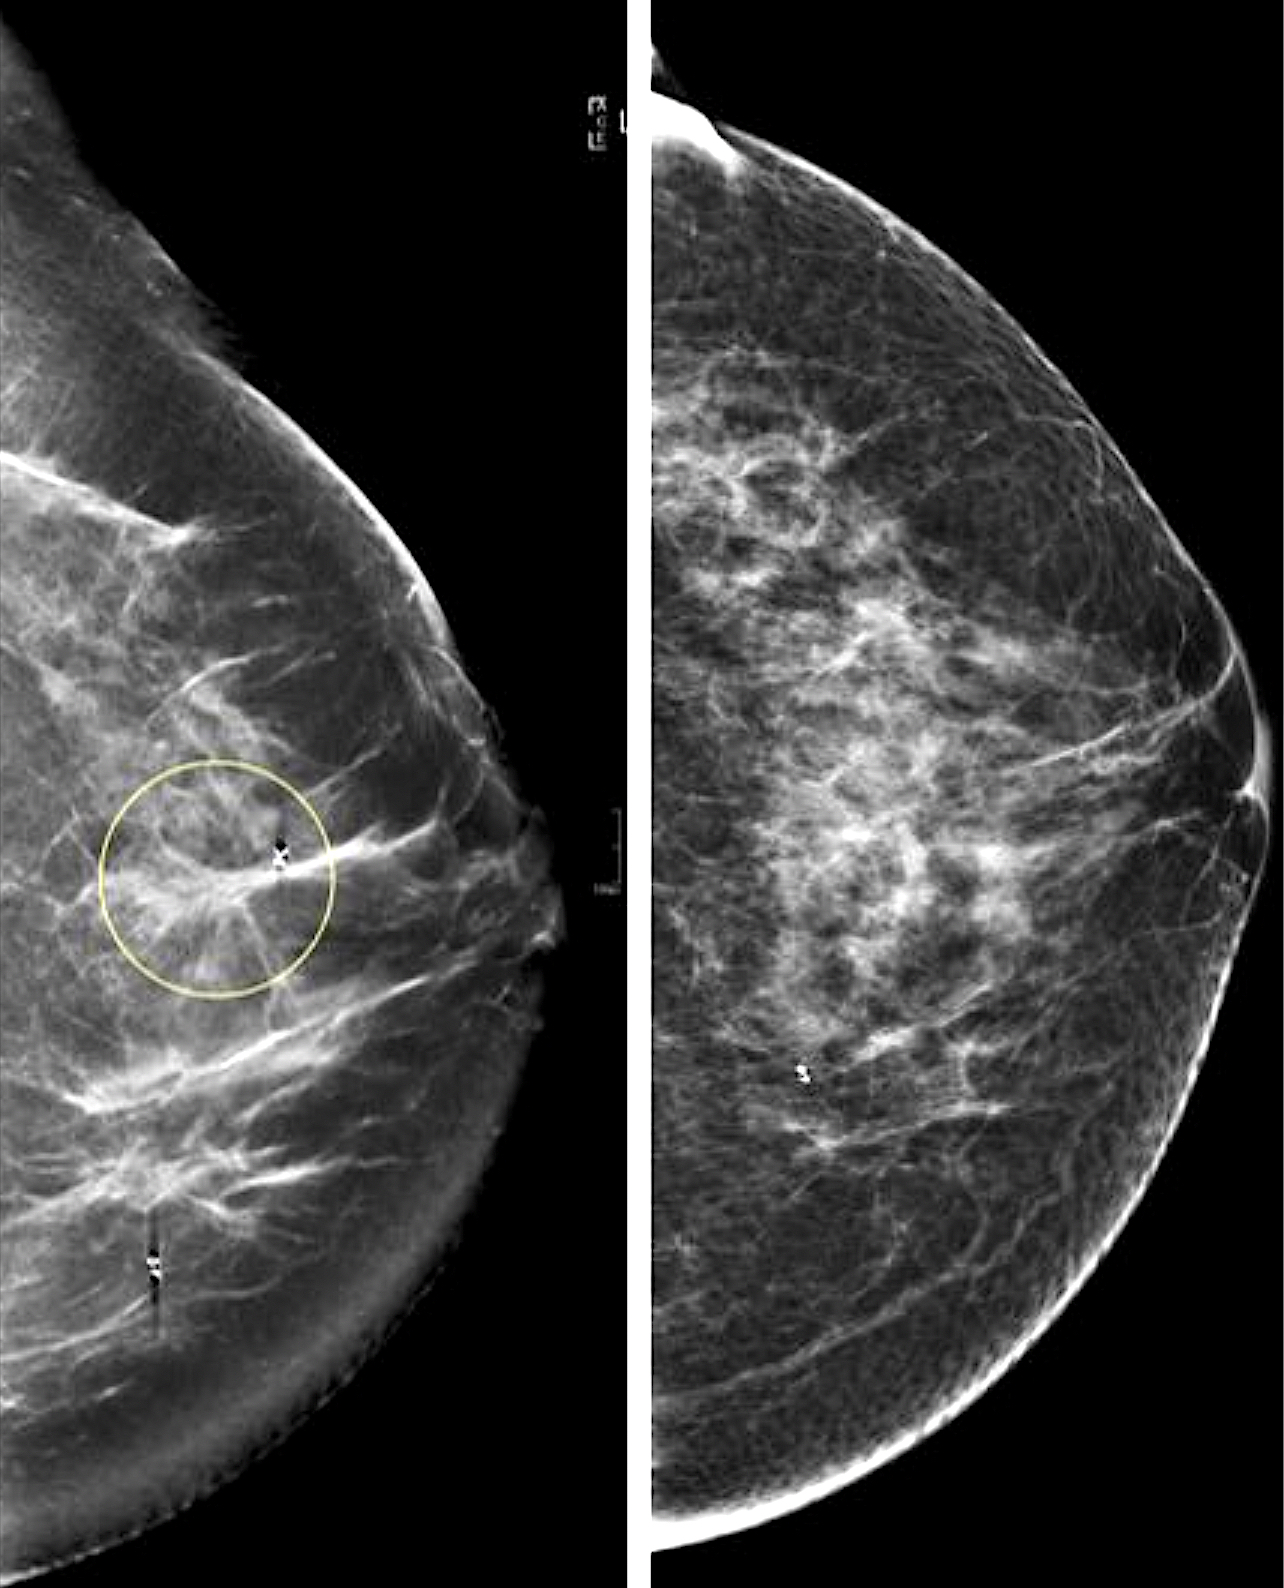

Рак Груди1 Фото

Рак Груди1 Фото 136 фото